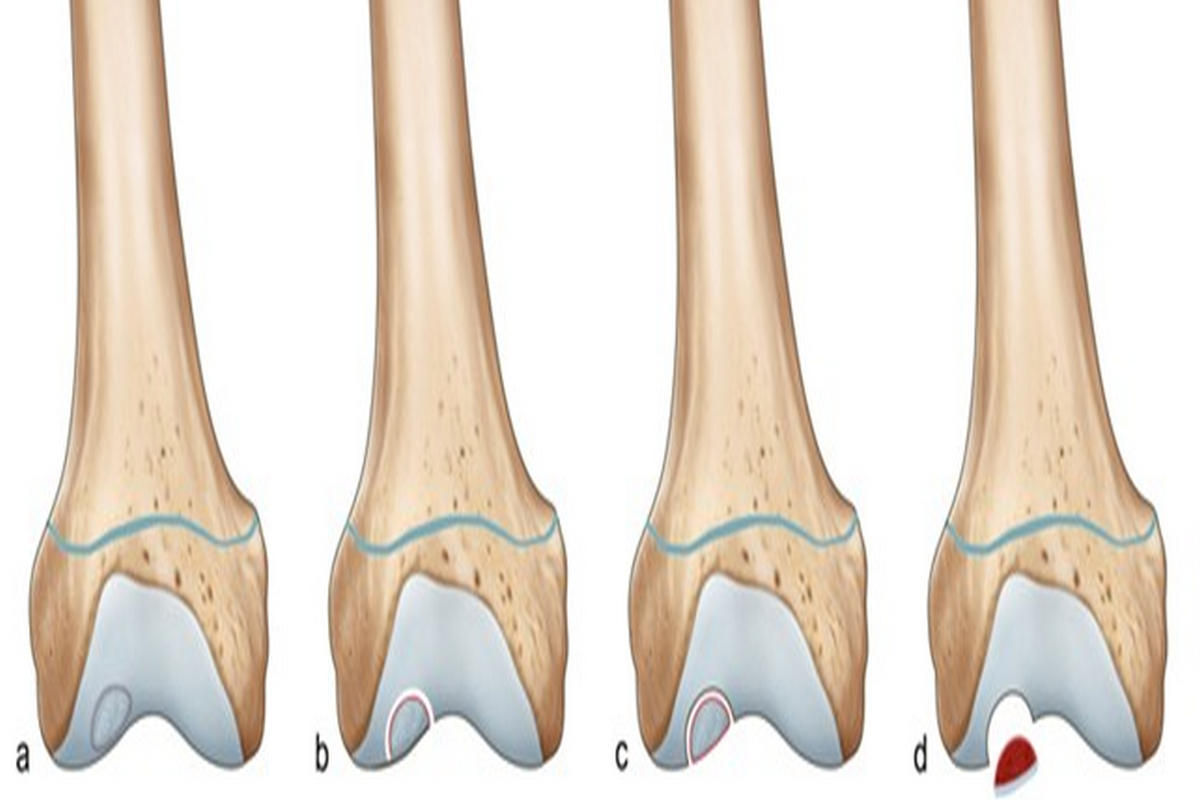

Επιπλέον, συγγενείς ή αναπτυξιακές διαταραχές της άρθρωσης, καθώς και εκφυλιστικές αλλοιώσεις σε μεγαλύτερες ηλικίες, μπορούν να συμβάλουν στην εμφάνιση οστεοχόνδρινων βλαβών. Οι αλλοιώσεις μπορεί να είναι επιφανειακές ή να επεκτείνονται σε όλο το πάχος του χόνδρου, συχνά με συμμετοχή του υποχόνδριου οστού.

Σε εκτεταμένες ή συμπτωματικές βλάβες ενδείκνυται χειρουργική αντιμετώπιση. Οι σύγχρονες τεχνικές περιλαμβάνουν αρθροσκοπικό καθαρισμό και λείανση της βλάβης, μικροκατάγματα που διεγείρουν τον σχηματισμό ινοχόνδρου, αυτόλογη μεταμόσχευση χονδροκυττάρων και μεταμοσχεύσεις οστεοχόνδρινων κυλίνδρων. Σε περιπτώσεις εκτεταμένης φθοράς μπορεί να εξεταστεί και η λύση της μερικής ή ολικής αρθροπλαστικής γόνατος.